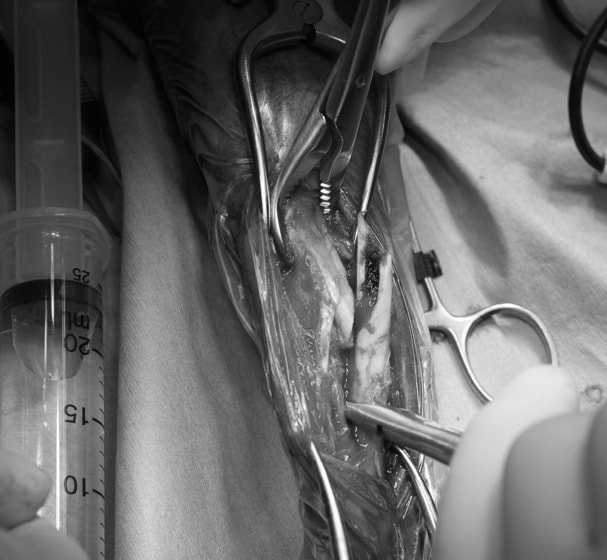

トイプードル 右遠位橈尺骨短斜骨折のALPSによる内固定

症例3:キルシュナーワイヤーのピンニングによる整復

ペルシャ猫 11ヶ月齢 雄

他院にて左大腿骨遠位の成長板骨折(salter-harrisⅠ型)が認められており、治療相談を目的として来院。当院にて、キルシュナーワイヤーを用いたピンニングにより骨折部位の整復を行いました。術後の経過は良好で、現在も経過観察中です。

Arthrex社のターゲティングデバイスを用いてピンニングの位置を調整することで、確実な固定を行っています。当院ではこの手術器具以外にも、人の手術にも使用される様々な器具を導入し、手術精度を高め、また医療メーカーと新しい器具の開発、試作にも取り組んでおります。